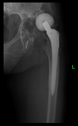

The radiological examination allowed us to verify the close bone-to-implant contact and the unchanged position of the implant during follow-up.

In all the cases operated with the above-described targeting procedure, the stems of the cups remained between the cortical bone surfaces without perforation of the linea terminalis, as shown by postoperative radiographs. There were no complicated surgical situations. In 16 cases, the wound healings were uneventful, and the hips were able to bear weight again after postoperative rehabilitation.